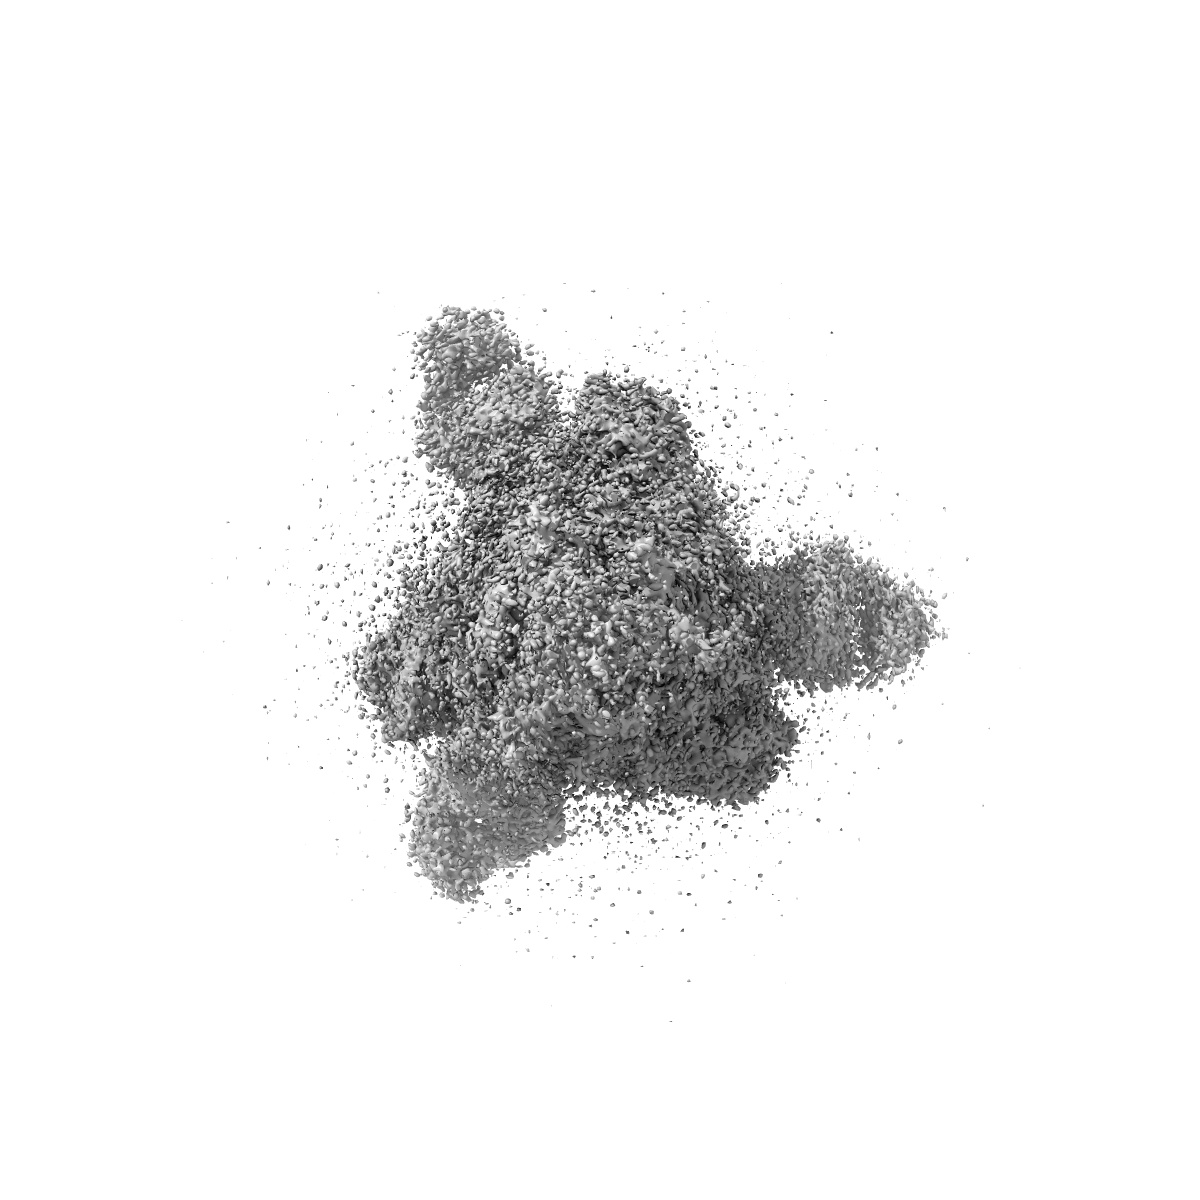

Cryo-EM structure of SARS-CoV-2 Omicron BA.4 S-trimer in complex with fab L4.65 and L5.34

Single-particle

2.85 Å